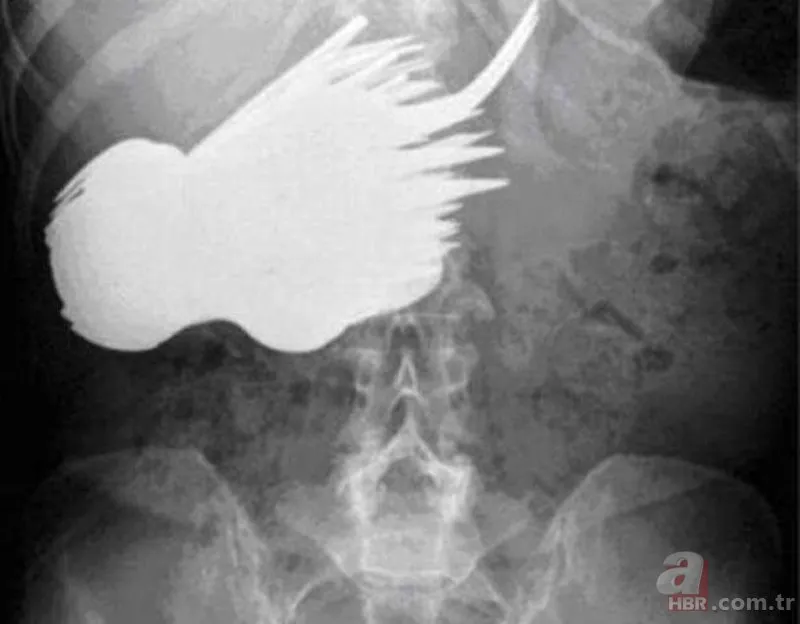

Bundan yaklaşık 30 yıl önce, Hollandalı bir kadının midesinden toplamda 78 adet çatal ve kaşık çıkartıldı. Bir an önce ameliyata alınan kadın şu açıklamayı yaptı: 'Neden bilmiyorum ama, gümüş şeyleri yemek konusunda feci bir istek duyuyorum, kendimi kontrol edemiyorum.'